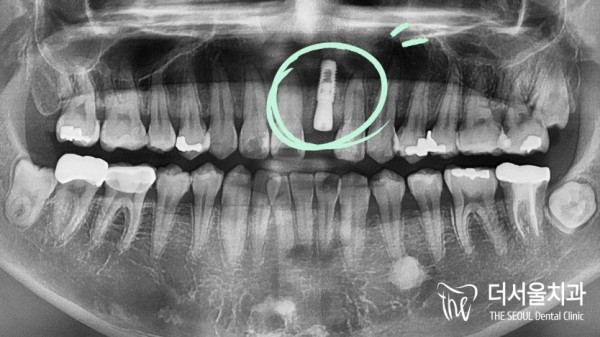

초반 임플란트를 통해 공간을 확보한 후에 임플란트 픽스쳐(인공치근)를

심어놓은 모습을 위의 이미지에서 확인하실 수 있습니다.

After freeing up space through the initial implant, the implant fixture (artificial root) was used

You can see the planted image in the image above.